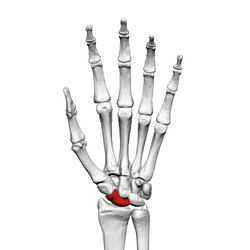

Scaphoid bone (left hand) 01 palmar view.png

Left hand anterior view (palmar view). Scaphoid bone shown in red.

The scaphoid bone is one of the carpal bones of the wrist. It is situated between the hand and forearm on the thumb side of the wrist (also called the lateral or radial side). It forms the radial border of the carpal tunnel. The scaphoid bone is the largest bone of the proximal row of wrist bones, its long axis being from above downward, lateralward, and forward. It is approximately the size and shape of a medium cashew.

The scaphoid is situated between the proximal and distal rows of carpal bones. It is located on the radial side of the wrist, and articulates with the radius, lunate, trapezoid, trapezium and capitate.[1]:176 Over 80% of the bone is covered in articular cartilage.[2]